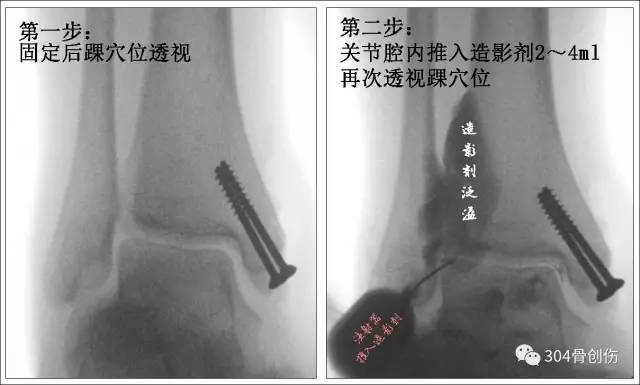

术中影像诊断新方法

Chertsey 试验

踝部骨折术中如何判断下胫腓分离程度?最常用的就是“拉钩试验(Cotton test)”,透视观察下胫腓之间距离。当下胫腓固定后,胫腓骨远端位置是否妥当?拉钩试验难以评判。最好的方法就是术中CT检查,但目前不是所有的手术室均有术中CT,多是靠术后CT检查后判断,一旦发现下胫腓位置关系不正确,相当一部分需要重新翻修,增加了患者的痛苦,也增加了手术感染风险。简单可靠的评估方式亟需在临床上推广。

英国Boyd 等人提出在术中判断下胫腓联合损伤或腓骨复位情况的新方法-Chertsey 试验,该文发表在Injury 杂志。

Chertsey(切特西)位于英格兰萨里郡兰尼米德区的一个集镇,位于泰晤士河畔。该文作者所在医院位于该地区,故名“Chertsey 试验”

Boyd 文献-Chertsey 试验

Robert P.R., Syed Zuhair Nawaz, Arshad Khaleel.A new assessment for syndesmosis injury – The ‘Chertsey test’Injury. 2016 Jun;47(6):1293-6.

注射针头国际标准

常规手术固定骨折,继而用细穿刺针(22G 腰穿针-相当于6.5号针头,内径0.41mm)在透视下插入踝关节前外侧关节腔,透视踝穴位下注入 2~4 mL 的造影剂(可以1:1盐水稀释)。若造影剂流向下胫腓联合区域,出现「泛溢」现象,说明造影剂渗至损伤的下胫腓联合。若无下胫腓联合损伤,造影剂则局限于踝关节区域,此即 Chertsey 试验阴性。

下胫腓无分离-关节腔内注入造影剂

下胫腓无造影剂泛溢

Chertsey 试验阴性

下胫腓分离-关节腔内注入造影剂

下胫腓出现造影剂泛溢

Chertsey 试验阳性

下胫腓固定准确-关节腔内注入造影剂

造影剂有时可少量渗入至下胫腓联合,但仍可看到一个清晰的踝关节边缘,而非 Chertsey 试验阳性时的「泛溢」表现。 Chertsey 试验可重复检查腓骨是否解剖复位,造影剂一般可在 10~15 min 内吸收。

有时, Chertsey 试验可发现三角韧带嵌入现象,可内侧切开处理韧带嵌顿,继而行腓骨固定。

Chertsey 试验见三角韧带嵌顿

作者强调:Chertsey 试验只能用于判断下胫腓联合是否存在损伤。与拉钩试验相同,Chertsey 试验并不能预测损伤程度,只有骨间韧带完全断裂才表现 Chertsey 试验阳性,所以在下胫腓联合轻度损伤时可表现为阴性结果,此试验最大意义-术中检验下胫腓固定是否准确。

友情提示:造影剂应做过敏试验!